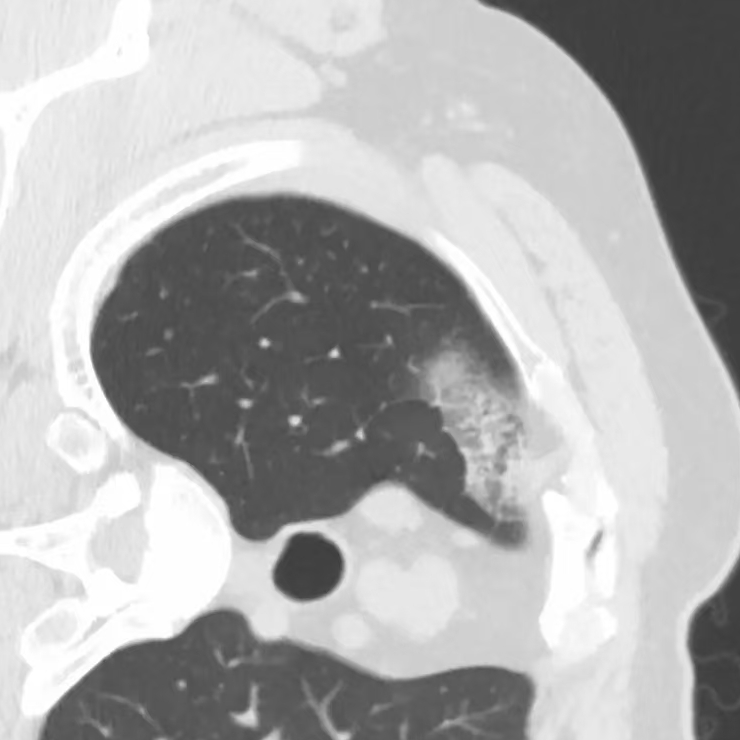

健康直通车: 健康是生命的宝贵财富,也是幸福生活的基石。为了更好地服务广大百姓,传播健康知识,葫芦岛市第二人民医院推出“健康直通车”专题栏目,将专业的医学知识以通俗易懂的方式传递给每一位市民,掌握科学的疾病预防方法,共同构筑健康中国的坚实基石。 什么是肺结节 肺结节是指肺内直径小于或等于3cm的类圆形或不规则形病灶,影像学表现为密度增高的阴影。大于3cm的称肿块。肺结节依其密度不同可分为实性结节、部分实性结节、磨玻璃结节,其中部分实性结节的恶性可能性最大,磨玻璃结节次之,实性结节尤其是小的实性结节结节最可能是良性的。 肺结节的常见病因 1、良性(约90%) 🔸 感染:结核、真菌、细菌性肺炎后遗留的瘢痕; 🔸 非感染:错构瘤(良性肿瘤)、炎性假瘤、血管瘤等。 2、恶性(约10%) 🔸原发性肺癌(如腺癌、鳞癌); 🔸转移性肿瘤(其他器官癌症转移至肺)。 如何根据影像判断肺结节性质 1、依据结节大小判断 🔸小于0.5cm的肺结节绝大多数都是良性的,属于微小结节。即使部分小于0.5cm肺结节是恶性的,但是适当的观察不影响预后。每年复查一次胸部CT就可以。 🔸大于0.5cm持续存在的纯磨玻璃结节,观察6个月,若持续存在,不管有无进展均多数是恶性的,视患者意愿,手术可以立即做也可观察至进展再做,不影响预后。 🔸大于0.8cm的部分实性结节恶性可能性非常大,应积极评估结节边缘毛刺、分叶、胸膜凹陷等征象。 🔸若实性部分大于0.5cm,恶性率显著提高。若在3~6个月随访期间实性部分增大或者总体部分增大,都可以考虑手术切除。而即使小于0.8cm的部分实性结节也需3个月就复查对比。 2、依据肺结节形态 如CT上提示病灶形态不规则、毛刺、分叶、胸膜凹陷、空泡征、血管集束征等,符合恶性肿瘤的征象。 🔸结节与正常肺组织之间界限非常清楚的恶性可能性大。 🔸结节密度不均呈混杂密度或均匀较大纯磨玻璃结节也基本是恶性的。 🔸有胸膜牵拉(不管是肺表面的脏层胸膜还是叶间裂部位的胸膜)的恶性可能性大。 🔸结节有浅分叶、细毛刺,密度较高而与周围肺组织边界不清的恶性可能性大。 🔸磨玻璃或混合磨玻璃结节存在小空洞的恶性可能性大。 🔸影像上似慢性炎表现,而没有炎症相关的其他异常,特别当所谓炎症区域内部或一侧与正常肺组织之间界限非常清楚的基本上是恶性的。 3、从结节发展情况来看 所有随访中增大进展的都需要考虑恶性可能,不进展而持续存在的纯磨玻璃结节也需考虑恶性。 葫芦岛市第二人民医院肺结节诊治中心孙振教授深耕肺结节领域四十余载,凭借对临床实践的执着钻研与深厚积淀,在肺结节精准诊断及鉴别诊断领域形成独到见解。他系统总结海量临床病例,创新性提炼出一套科学化、规范化的肺结节全周期诊疗体系,尤其在早期微小结节的影像特征识别、良恶性风险分层等方面积累了丰富经验,为众多患者提供了精准、高效的诊疗方案。 人民医院·人民名医 孙振 主任医师 三级教授 ·葫芦岛市第二人民医院胸外科主任、肺结节诊治中心主任 ·中国医科大学客座教授 ·原央企总医院著名胸外科专家 ·辽宁省医学会胸外科委员 ·辽宁省抗癌协会肺癌专业委员会委员 ·辽宁省细胞生物学学会食管癌专业委员会理事 ·主持多项科研成果获科技成果奖、科技进步奖、国家专科奖项 医学成就 从事胸外科临床工作近40年,担任胸外科首席专家及科室主任20余年,是我省胸外科领军人物,推动肺癌、食管癌等胸部肿瘤外科的规范化诊疗,在央企总医院牵头成立了肺结节诊疗中心,率先开展CT引导下肺内小结节定位切除,既确切完整切除肺内小结节,又降低肺功能损害。 专业特色 擅长肺癌、食管癌的外科手术和综合治疗,在各类高难度胸外伤手术治疗、胸腔镜微创手术、胸腺瘤手术及复杂并发症处理方面具有高深造诣,尤其擅长肺癌早期诊断,胸部小结节CT早期肺癌的鉴别等。完成各类高难度胸外科手术5000余例,其中微创手术占比达90%,治愈率达98%,多项业务填补省内空白。 开展的高难手术 胸腔镜肺部结节微创手术、肺癌根治术、食管癌根治术、各种纵隔肿瘤切除术、胸骨后甲状腺手术及胸部复合性外伤的抢救手术等。